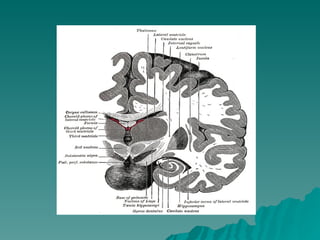

DISPOSIÇÃO  ANATÕMICA Núcleo Caudado  = Massa volumosa e alongada, relacionada  em toda sua extensão com os ventrículos laterais Cabeça  Corno Anterior Corpo  Assoalho Central Cauda  Extremidade Anterior do corno inferior A cabeça do núcleo caudado se funde com a parte anterior do núcleo lentiforme

DISPOSIÇÃO ANATÕMICANúcleo Caudado = Massa volumosa e alongada, relacionada em toda sua extensão com os ventrículos laterais Cabeça Corno Anterior Corpo Assoalho Central Cauda Extremidade Anterior do corno inferior A cabeça do núcleo caudado se funde com a parte anterior do núcleo lentiforme

LENTIFORME = FORMA DE UMA CASTANHA DO PARÁ Não aparece na superfície ventricular – Profundo Medialmente se relaciona com a cápsula interna  Separa do caudado e do tálamo Lateralmente  córtex da ínsula, separado pela  substância branca e pelo claustrum DIVIDIDO – Putamem = lâmina medial Globo pálido = lâmina mais lateral e branca  Coloração mais clara = fibras mielínicas que a atravessam PARTE EXTERNA GLOBO PÁLIDO  lâmina medular  medial PARTE INTERNA

LENTIFORME = FORMADE UMA CASTANHA DO PARÁ Não aparece na superfície ventricular – Profundo Medialmente se relaciona com a cápsula interna Separa do caudado e do tálamo Lateralmente córtex da ínsula, separado pela substância branca e pelo claustrum DIVIDIDO – Putamem = lâmina medial Globo pálido = lâmina mais lateral e branca Coloração mais clara = fibras mielínicas que a atravessam PARTE EXTERNA GLOBO PÁLIDO lâmina medular medial PARTE INTERNA